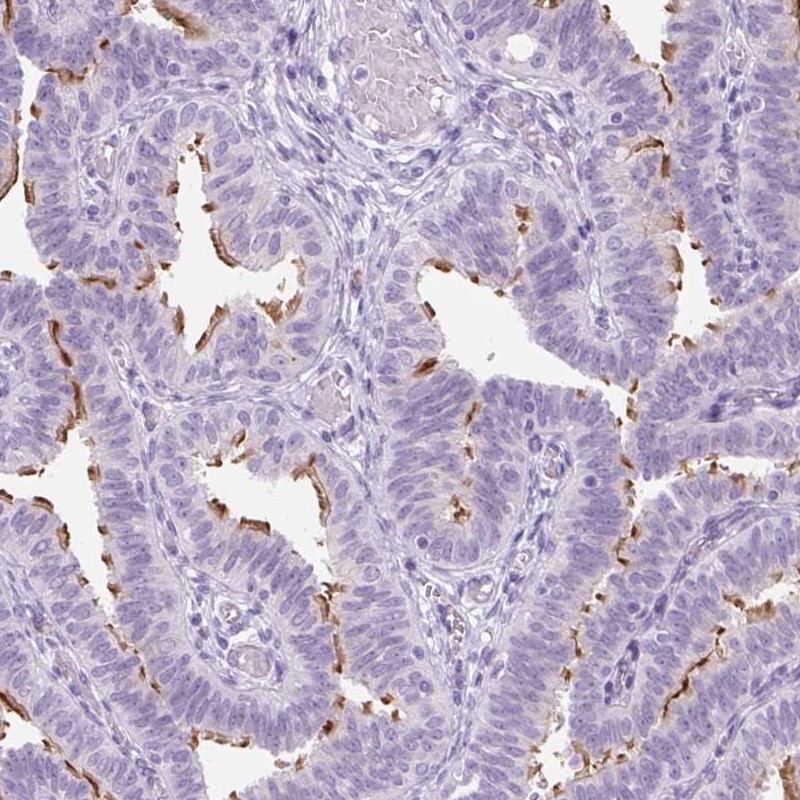

Immunohistochemical staining of human fallopian tube shows strong membranous positivity in glandular cells.